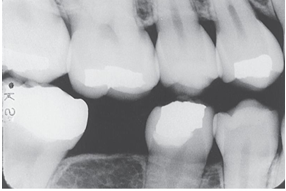

What is the problem with this Overlapped contacts X-ray?

Central ray not directed through the interproximal spaces

How would you resolve this Overlapped contacts X-ray?

Direct the x-ray beam through the contacts